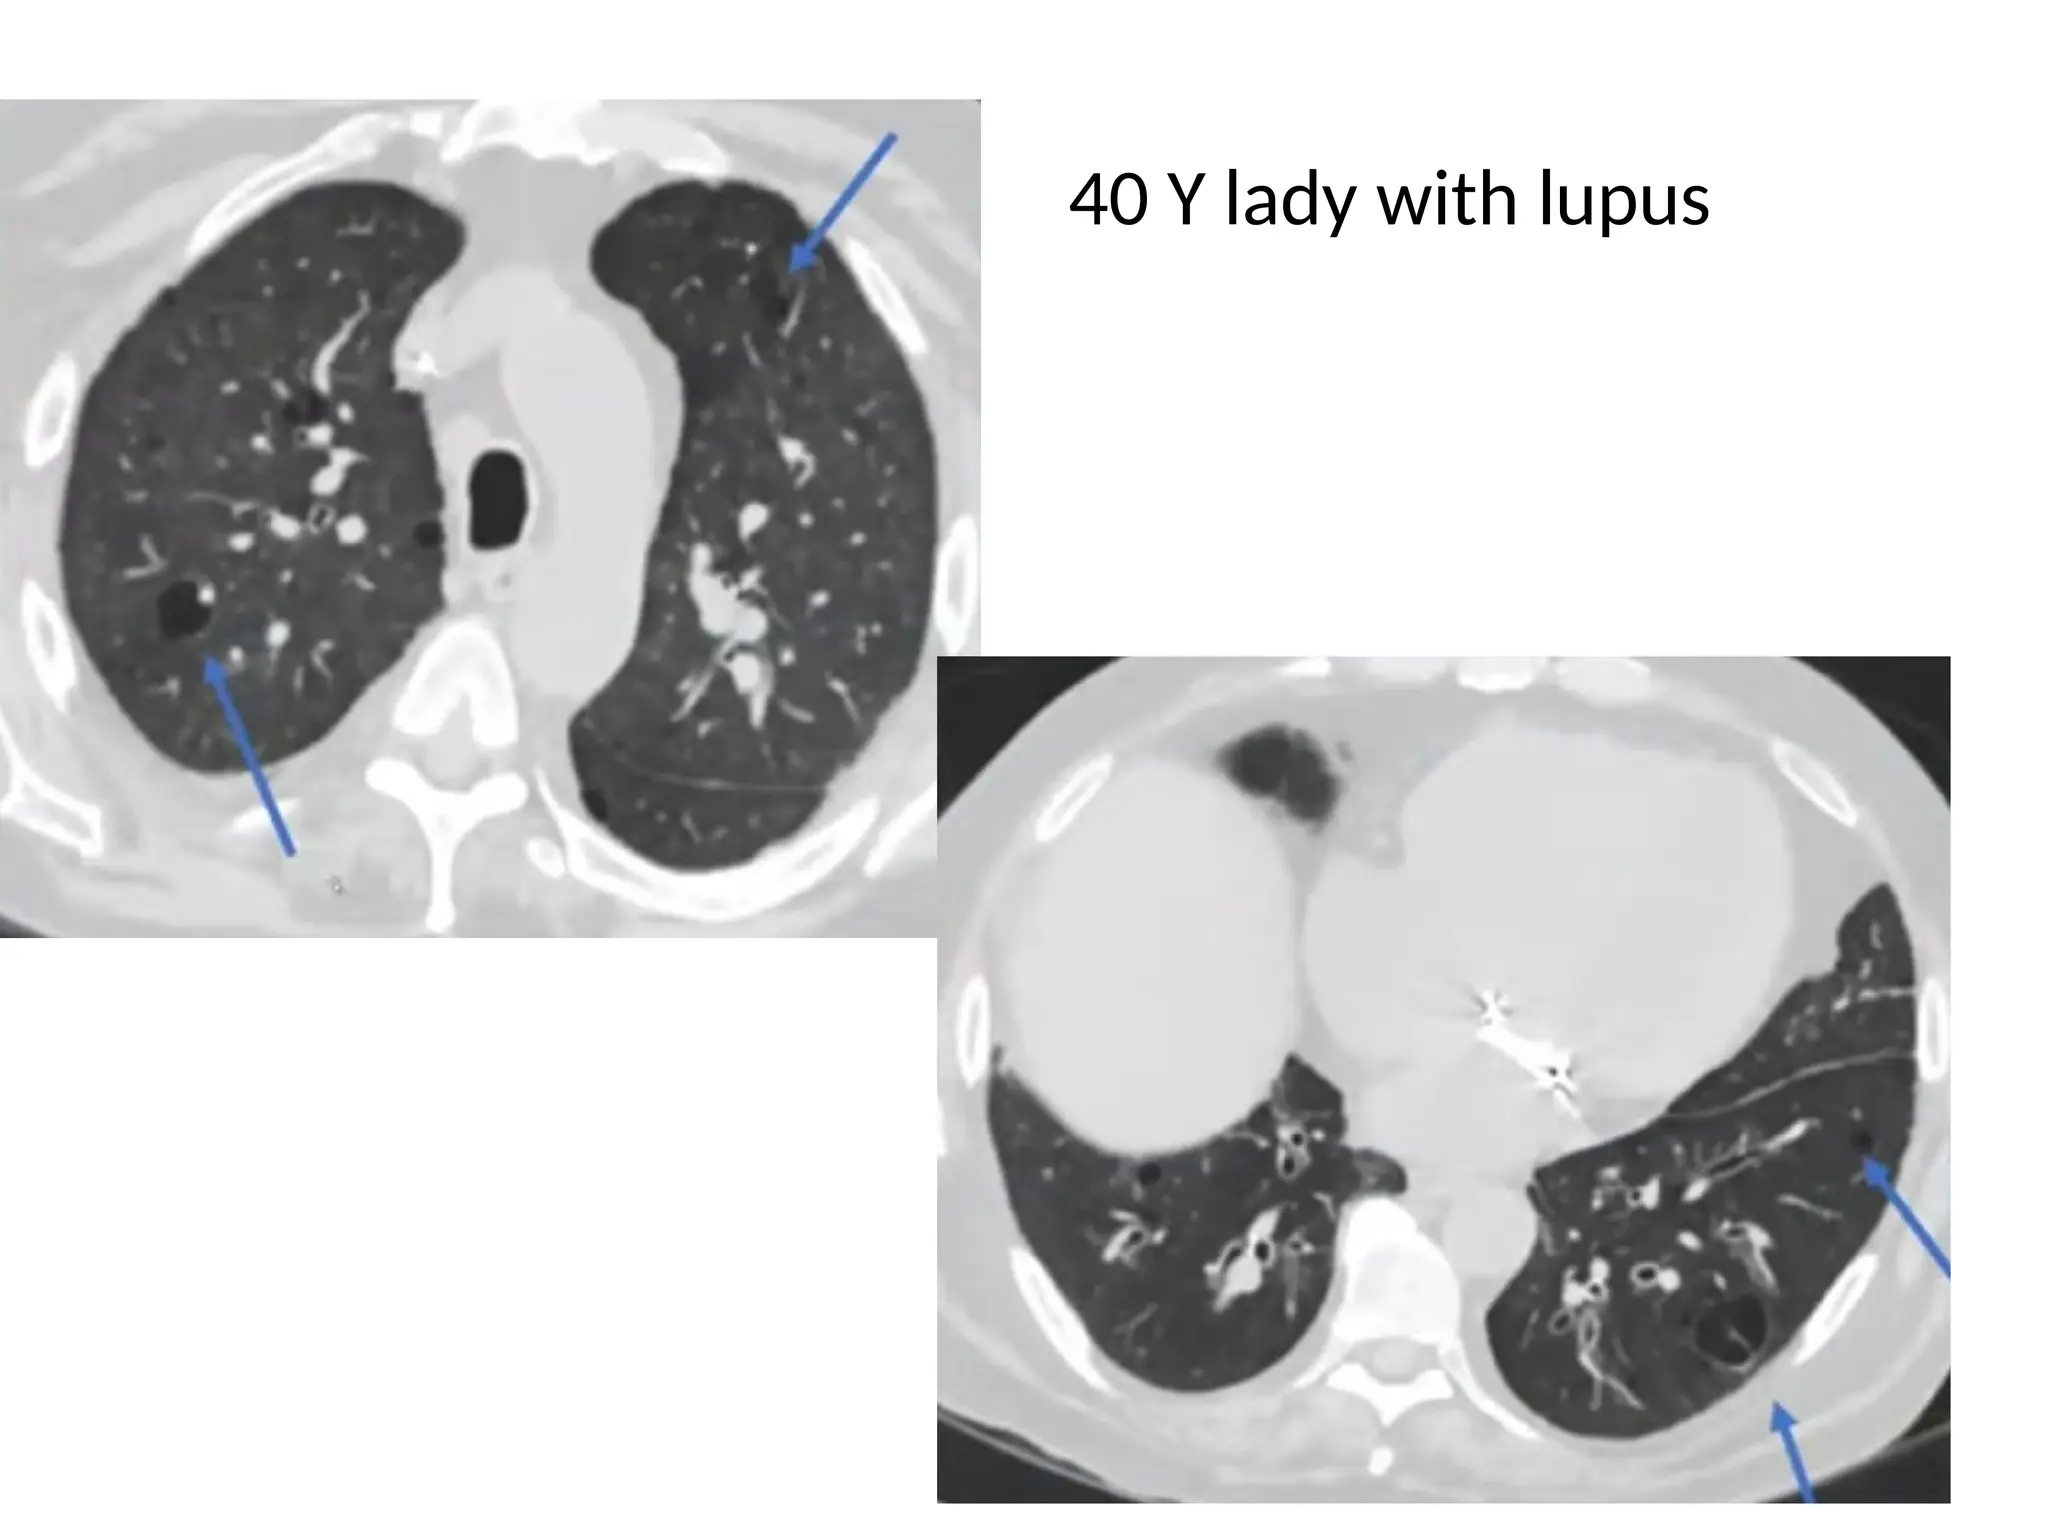

40 Y lady with lupus

Lymphocytic Interstitial Pneumonia • Females>> Males, 5th decade of life • Thin walled cysts in lower lobe predominance. • The cysts are perivascular in location. • Associated with: • Autoimmune diseases, AIDS • GGO, septal and bronchovascular bundle thickening

40 Y ladywith lupus